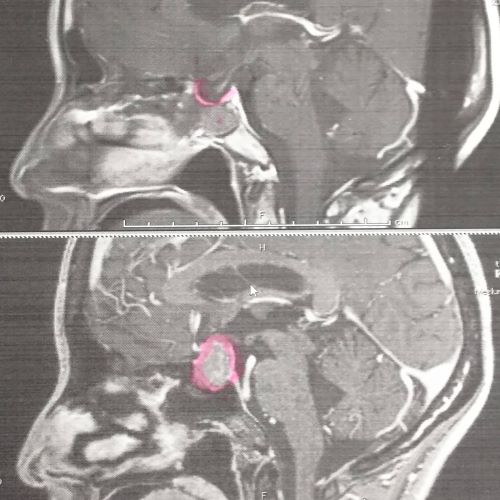

丁寧に横顔バージョンにもマーカー。

毎回お世話かけます、先生。

腫瘍がなくなって、下垂体が本来の位置に戻ってきました!

素人には分からないけど、